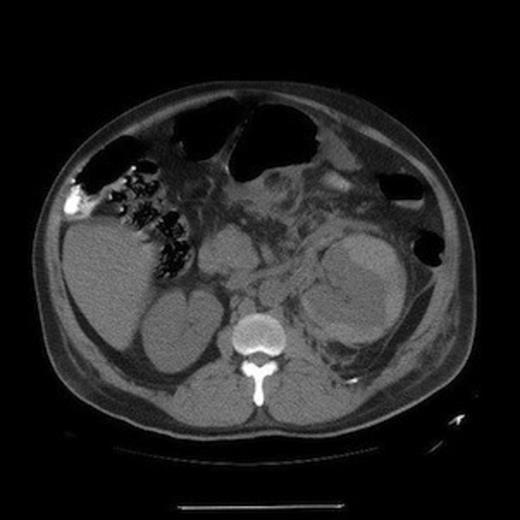

A 53 year-old-male patient with a history of diabetes and undiagnosed HIV presented with 24 hours of back and left sided abdominal pain. There was no history of trauma. On physical exam the patient had a distended abdomen and was moderately tender to palpation. He was found to be anemic with a haemoglobin and haematocrit of 7.2 gm/dL and 21%, respectively. In addition, the patient’s serum potassium was 7.7 mmol/L and he was in acute renal failure with a BUN of 59 mg/dL and serum creatinine of 4.1 mg/dL. The most recent laboratory values two years prior revealed a BUN and Cre of 15 mg/dL and 1.0 mg/dL, respectively. A computerised tomography scan of the abdomen and pelvis demonstrated a large left sided perinephric capsular haematoma without other significant abnormalities of the kidney (Figure 1). The patient was admitted to Intensive Care Unit for resuscitation and treatment of the hyperkalemia. Despite transfusion of packed red blood cells and correction of the serum potassium (4.9 mg/dL), the patient remained haemodynamically unstable and was subsequently taken to the operating room for an exploratory laparotomy.

CT scan of abdomen demonstrating a left perinephric capsular hematoma with retroperitoneal stranding